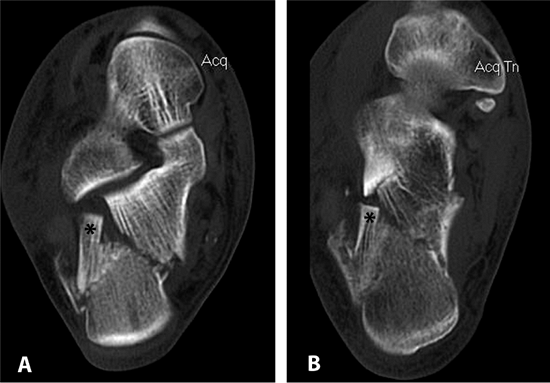

The axial images are used to classify the fracture and to evaluate the

fracture anatomy. The surgeon should make note of pertinent anatomic

points such as the position and integrity of the tuberosity, the

location and number of fractures in the posterior facet, displacement

of the lateral wall, the location of medial-wall comminution or

fracture lines, the size of the sustentacular fragment, fractures in

the anterior calcaneus, the presence or absence of an anterolateral

fragment, and the position of the peroneal tendons (dislocated or not) (Figs. 35.3 and 35.4).

![]() |

Figure 35.10. CT scan of fracture. The superolateral fragment (*) is seen on both the semicoronal (A) and transverse (B) projections.